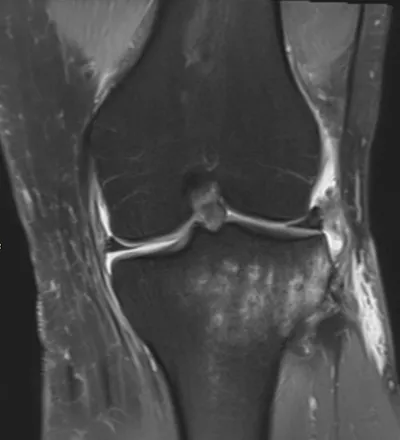

Meniscal Tear Radiology Images

Browse 4 medical images tagged with meniscal tear. This collection includes various imaging modalities for medical education and reference.

- This collection contains 4 radiology images related to meniscal tear, including various imaging modalities such as X-rays, MRIs, CT scans, and ultrasound images commonly used in medical diagnosis and education.